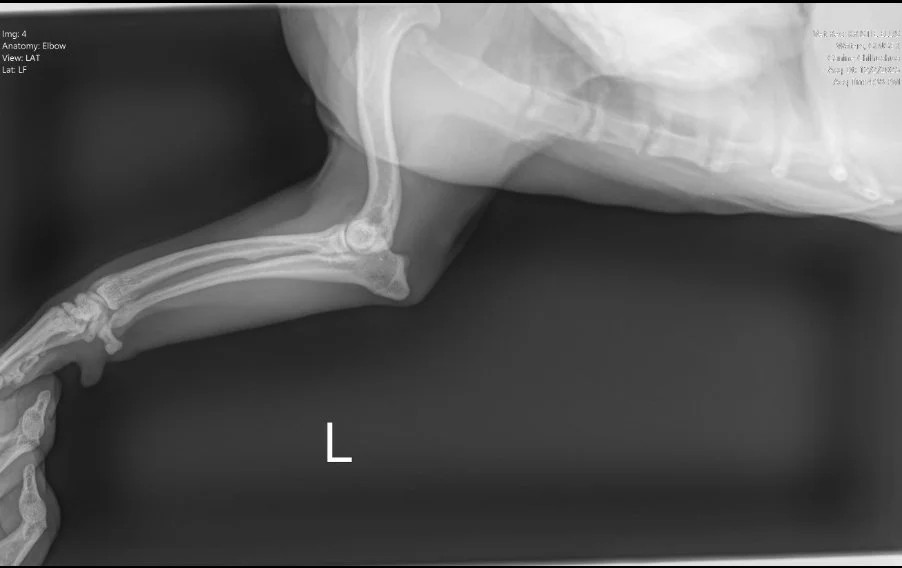

Image 2. Lateral radiograph of the left forelimb.

Radiographs (Images 1–4) of the left forelimb, including the carpus, elbow, and shoulder identified:

• Mild degenerative joint disease (arthritis)

• Decreased shoulder joint space

• No fractures, masses, or bone lysis

Based on these findings, Ginger was treated for osteoarthritis. However, her clinical progression did not match the imaging results.

👉 This mismatch is critical. Radiographs are excellent for evaluating bone, but they cannot assess nerve roots, the spinal cord, or most soft tissue structures.